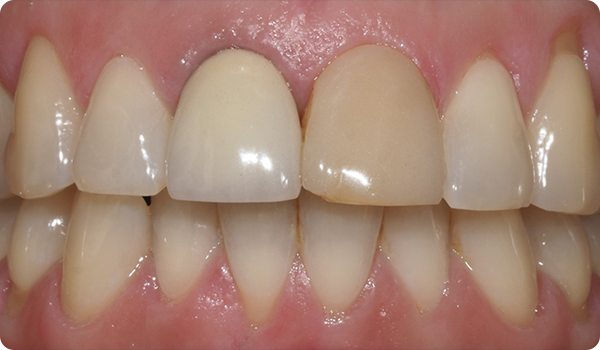

Med små rörelser korrigeras positioner och förbereder den mest lämpliga och konservativa estetiska behandlingen för dina patienter.

Att justera tänder med Right är den perfekta och mest konservativa grunden för framtida blekning eller facettbehandlingar som kommer att föra patientens leende till perfektion.